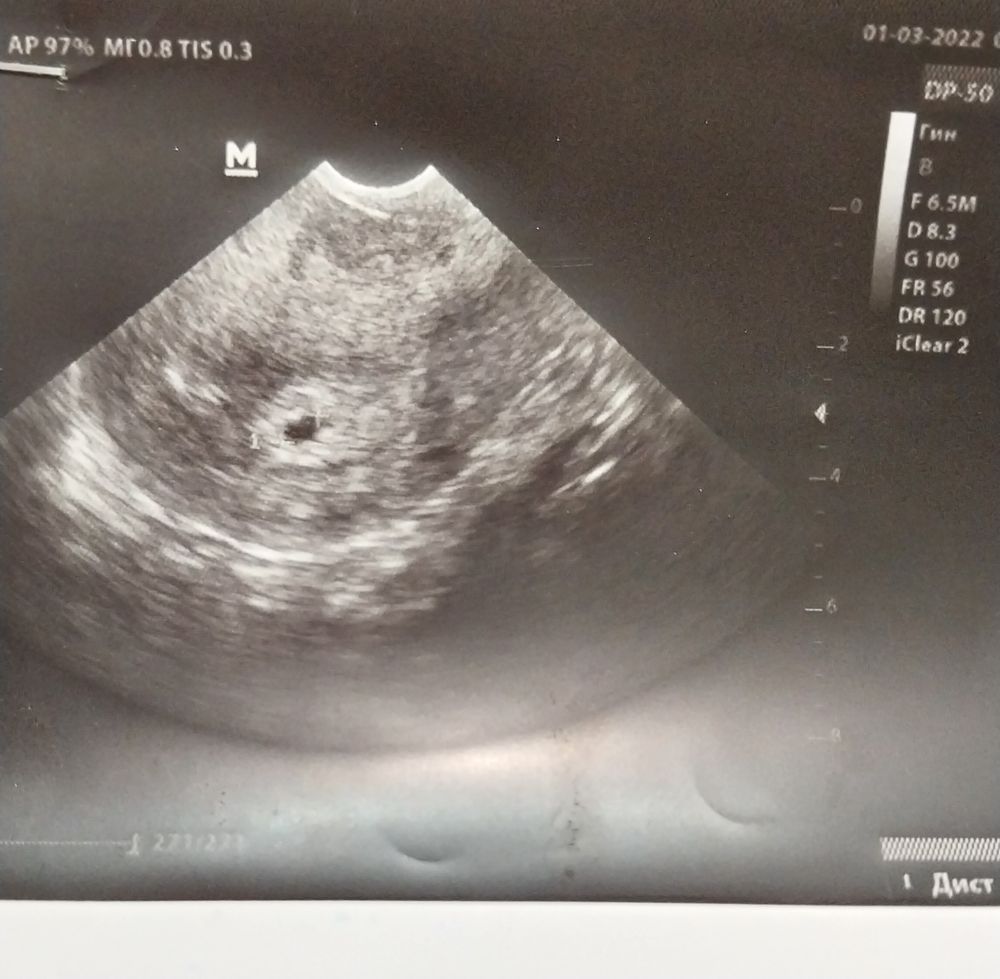

На узи я конечно сходила как договаривались 01.03...но оно меня не обрадовало как и позитивно настроенного врача ((( позитива у нее поубавилось резко. Да пя выросло, но не на столько на сколько должно было за 11 дней...всего на 3-4 мм.

Вот мой эмбрион, а говорили анэмбрионию. Я понимаю что замер, но диагноз неверный сказали, а при хорошем аппарате увидели.